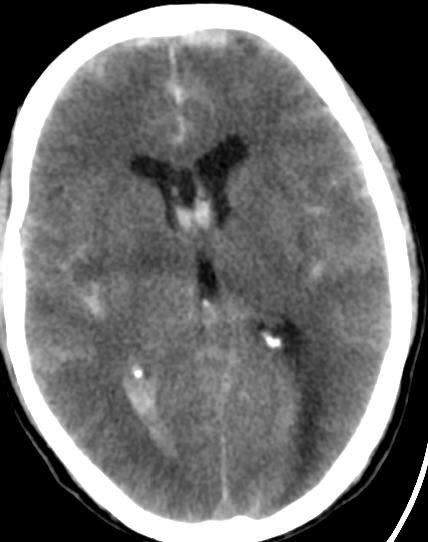

Phình mạch não là sự giãn khu trú bất thường của một động mạch não, là hậu quả của thiếu lớp cơ trong của thành mạch máu. Thành mạch yếu, giãn phình ra và trở nên mỏng, phát triển có thể dẫn đến vỡ đột ngột mà không báo trước, gây xuất huyết dưới nhện (SAH) – một biến cố nguy hiểm tính mạng, để lại di chứng nặng nề hoặc tử vong.

Phình mạch não chưa vỡ khá phổ biến trong dân số, chiếm khoảng 3,2% dân số người lớn trên toàn thế giới, tỷ lệ vỡ phình hàng năm của phình mạch não là 0,25%.